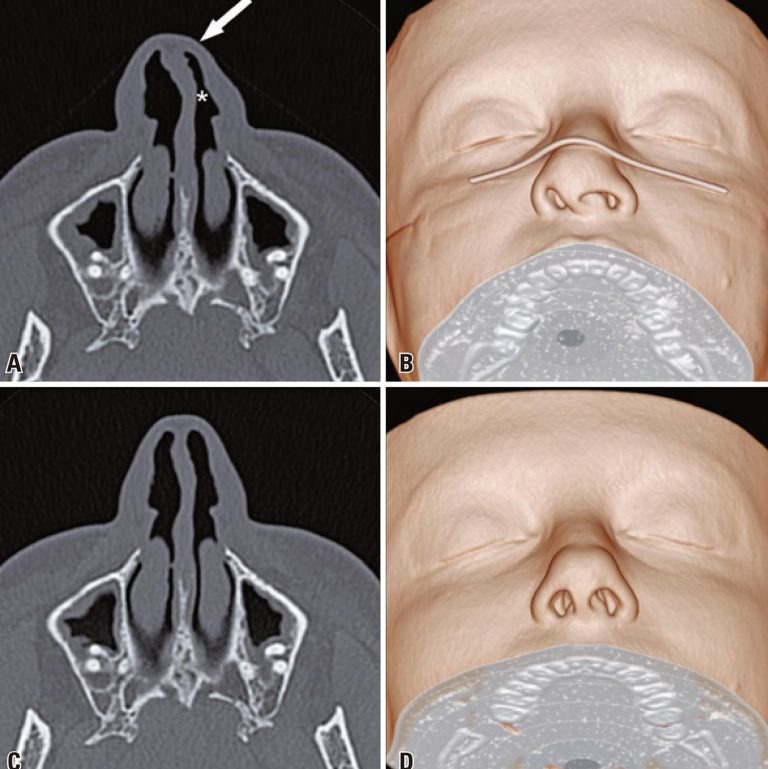

Nasal deformation by face masks on computed tomography

The widespread use of face masks is an essential tool for slowing the spread of the coronavirus disease 2019 pandemic and its adoption is recommended by the World Health Organization (WHO).() During the pandemic, several computed tomography scans of patients wearing face masks showed prominent nasal deformation, such as nasal septal deviations and nasal airway narrowing, which were absent in examinations of the same patients performed before the pandemic (). Therefore, care should be taken when evaluating the imaging examinations of the nasal region of patients wearing face masks.